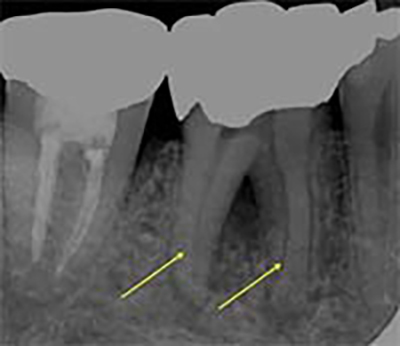

このどれか1つが欠けるだけで再発リスクが高まります。

側枝の取り残し

![]() |

| 術前 | 当院にて根充 |

そこで当院では、「成功率に直結する全7工程を、例外なく毎回行う」という標準化(Standardization)を徹底しています。

この標準化こそ、他院で治らなかった歯でも改善する可能性が高い理由です。以下では、当院の全工程を詳しくご紹介します。